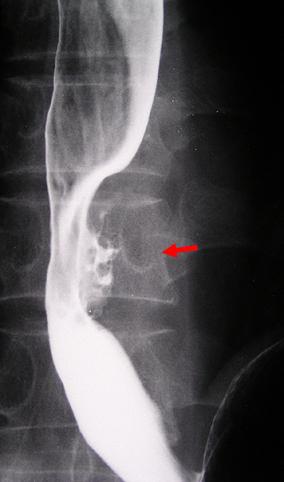

Cáncer avanzado de Esófago tipo 3, que acompañó metastasis en la pared de estómago, a ganglios linfáticos.

Tumor Epitelial Maligno/Carcinoma a Células Escamosas

esófago/inferior

Rayos X

Tipo 3(Tipo ulcerado de bordes infiltrados)/

35 - 40

s(a)